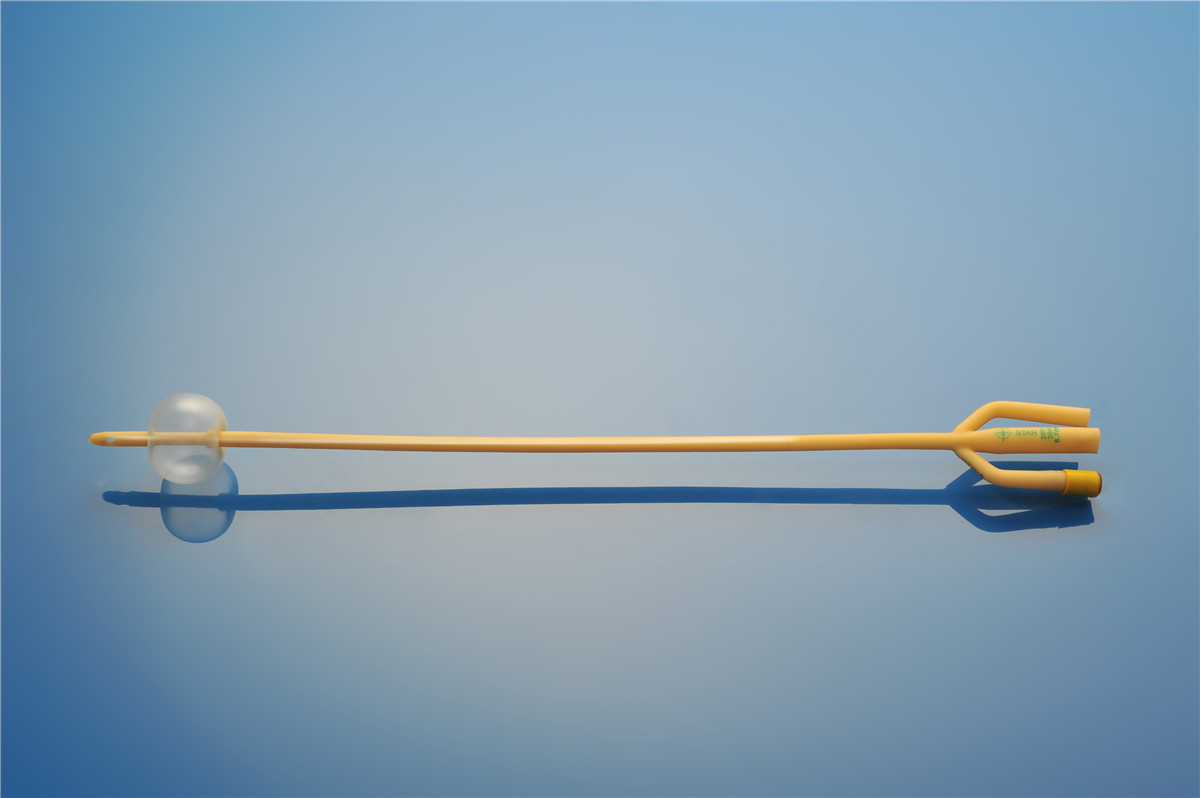

【產品名稱】一次性使用無菌導尿管(取樣型使用) 【型號】三腔氣囊取樣型 【規格】:16FR-26FR 【主要結構�、性能】由膠乳為主要原材料制成�,可配卡片。

型號:三腔氣囊標準型規格:三腔氣囊標準型:16Fr(30mL)、18Fr(30mL)���、20Fr(30mL)���、20Fr(50mL)、22Fr(30mL)���、22Fr(50mL)���、24Fr(30mL)、24Fr(50mL)�、26Fr(30mL)。結構及組成/主要組成成分:產品由導尿管����、水潤滑包(選配)組成。三腔由球囊腔充起錐...